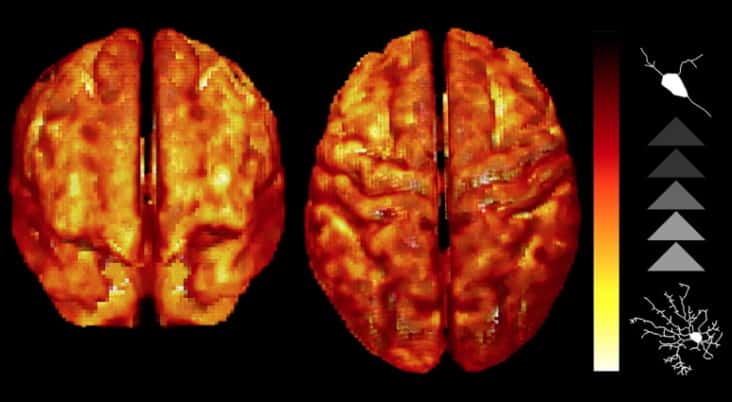

Read article: Ultralow-field MRI scanner could improve global access to neuroimaging

Ultralow-field MRI scanner could improve global access to neuroimaging

A low-cost, low-power, shielding-free, ultralow-field MRI scanner produces high-quality brain images